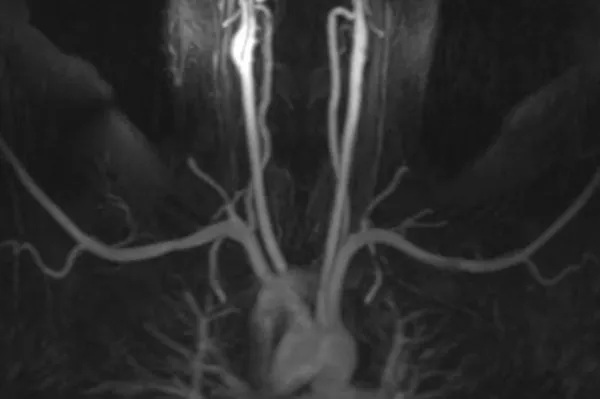

MR venography (MRV) can be performed in two ways. First is direct MRV. The physician injects contrast into a small arm vein. Shortly thereafter, the MRI scanner creates images as the contrast passes through the arm and chest. Direct MRV shows only veins, and only in one arm. In contrast is indirect MRV. Again, the physician injects contrast into a small arm vein. In contrast to direct MRV, scanning begins after a delay. First, injected contrast travels through the heart, the lungs, the arms, and returns through the arm veins. At this time, the MRI scanner creates images, showing both arteries and veins, in both arms. MRV shows the veins while eliminating other structures. MRV requires no radiation. If used in conjunction with MRI, superb soft tissue detail is available. Excellent depiction of fibrous bands, muscle anomalies, bones, and brachial plexus is possible with the combination of MRV and MRI.

This patient had an MR angiogram, followed by an MR venogram. Slide the handle side to side to see the difference between the two studies.

Before image alt After image alt